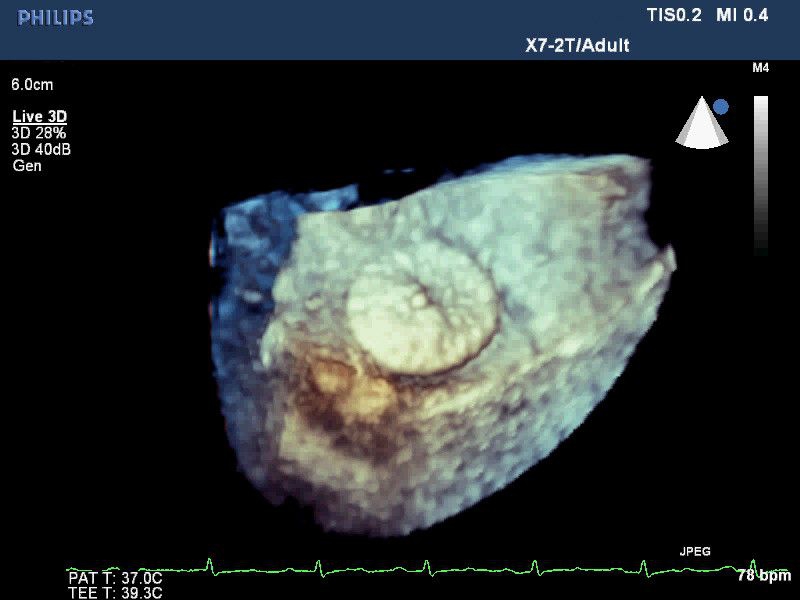

• Live 3D TEE: Эта функция позволяет проводить чреспищеводную эхокардиографию в режиме реального времени, что позволяет оценить механические сокращения сердца с точностью, необходимой для оценки результатов хирургического вмешательства.

• Чреспищеводная эхокардиография

• Чреспищеводный УЗИ датчик Philips Х7-2T